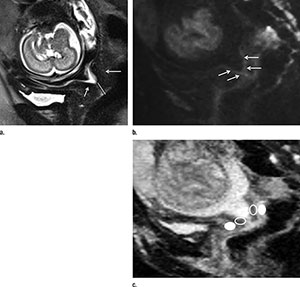

Cervical subglandular apparent diffusion coefficient (ADC) at MRI is associated with impending preterm birth in patients with a short sonographic cervix, according to new research published online in the journal, Radiology.

Gabriele Masselli, M.D., from Umberto I Hospital Sapienza University in Rome, Italy, and colleagues used pelvic 1.5-T MRI to study 30 pregnant women who had a sonographically short cervix. ADC values of the subglandular and stromal cervix, and the difference between both, were correlated to the interval to delivery.

Eight (27 percent) of the 30 patients delivered within six or seven days after MRI, and 22 (73 percent) of them delivered between 18 and 89 days after imaging. Overall, 19 (63 percent) of the patients experienced preterm delivery after less than 32 weeks of gestation.

“Our results indicate that a high ADC recorded at the level of the subglandular area of the cervix is associated with imminent delivery in asymptomatic patients who have a short cervix. This can be particularly useful in the acute care of patients who have a sonographically short cervix and positive fetal fibronectin test results in the early third trimester of pregnancy,” the authors write.